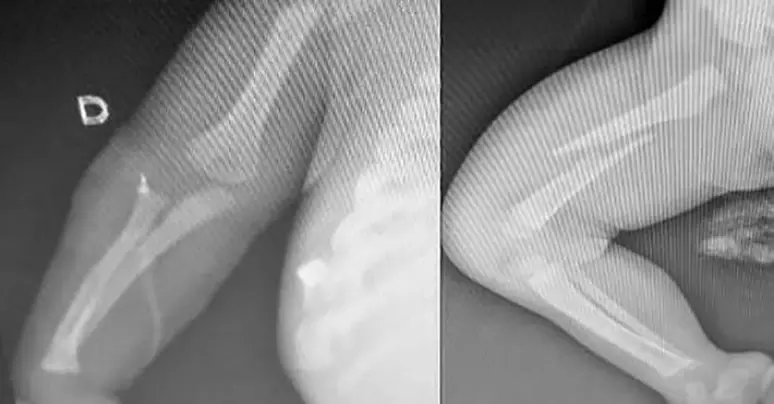

Os exames apontaram que a criança apresentava fraturas nos braços, fêmur e costela, como mostram os exames, além de perfuração pulmonar e hematomas pelo corpo. Desconfiando de maus-tratos, os policiais acionaram o Conselho Tutelar que, por sua vez, pediu apoio à Guarda Civil Municipal.